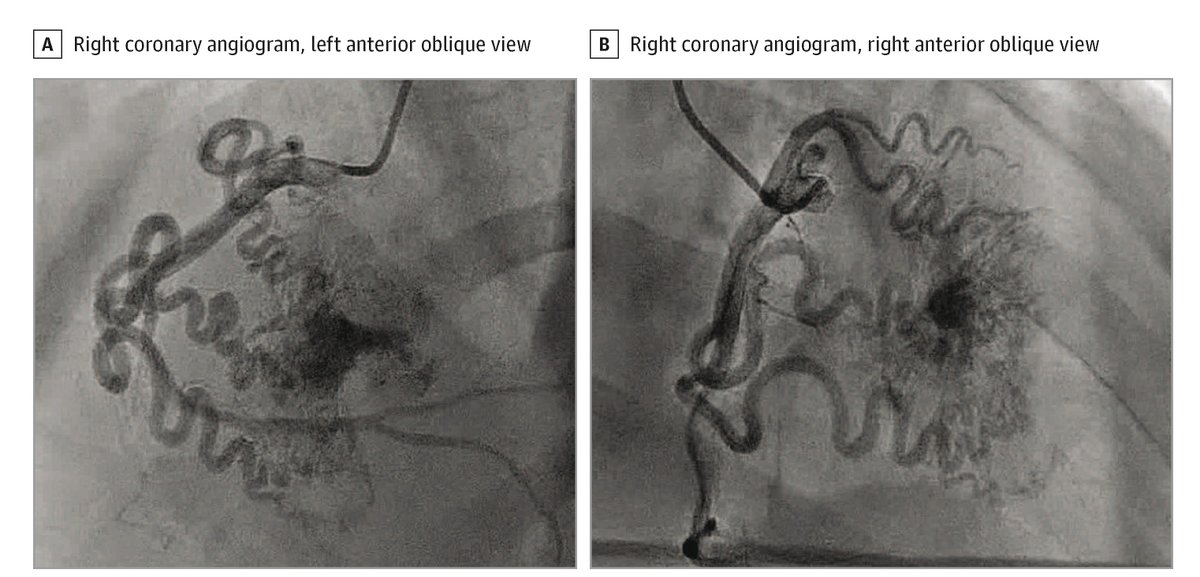

#CoronaryCameralFistulas should be considered in patients presenting with myocardial infarction and nonobstructive coronary arteries, as large fistulas can lead to significant cardiac complications. ja.ma/4bi82zc